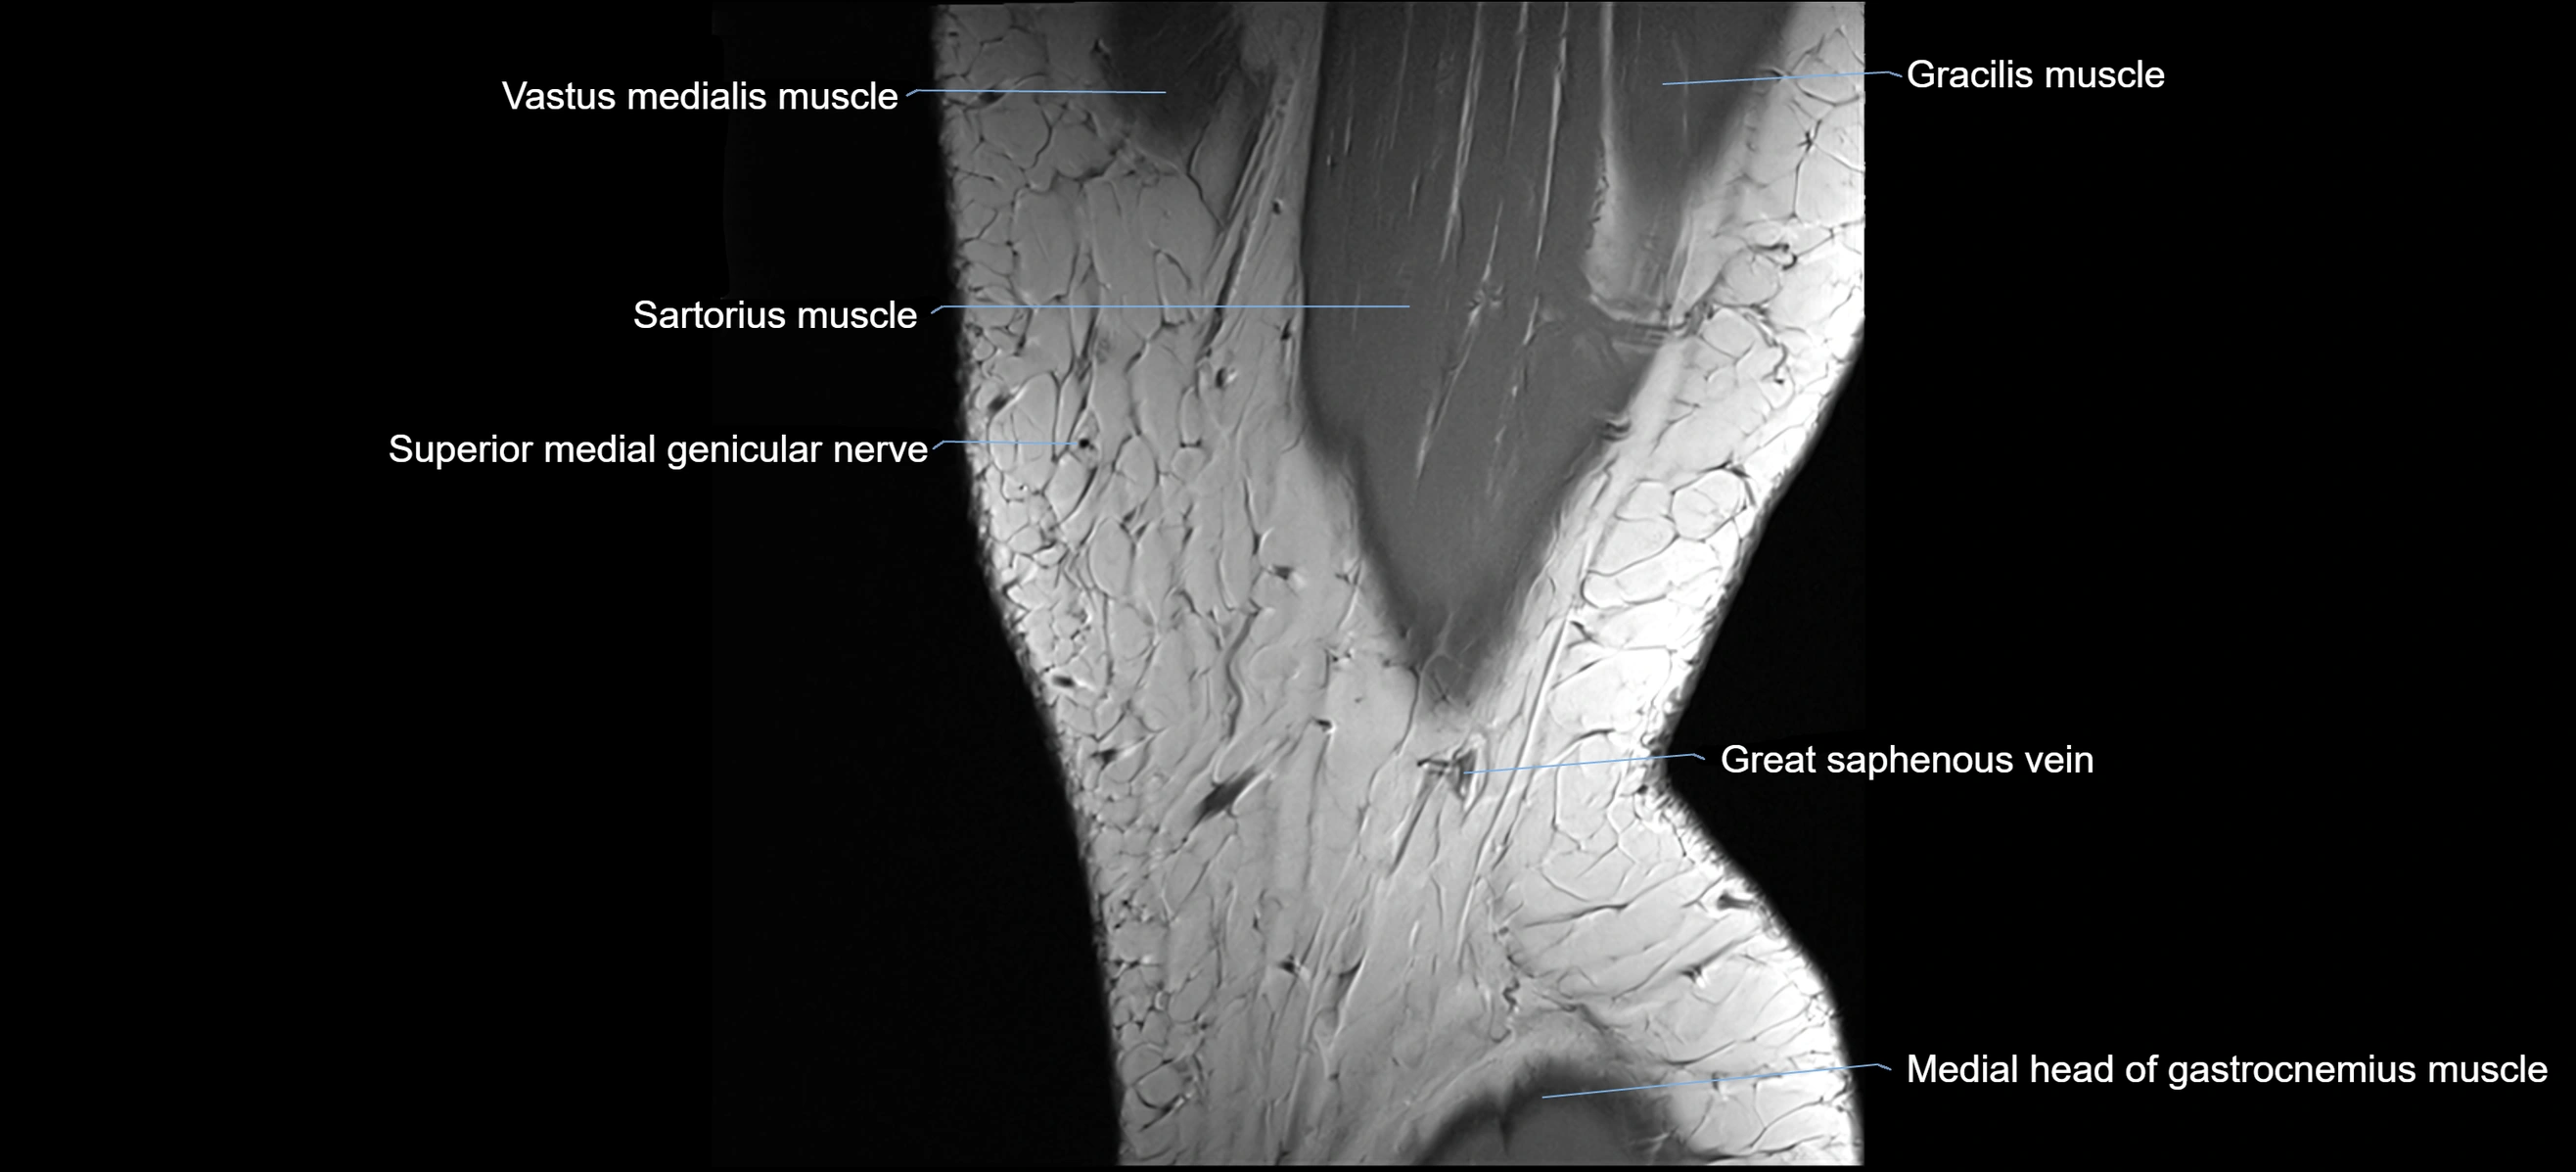

- Vastus medialis muscle

- Sartorius muscle

- Gracilis tendon (Distal)

- Medial head of gastrocnemius muscle

- great saphenous vein